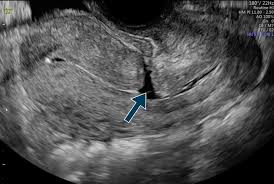

- Sau khi mổ lấy thai, một số ít thai phụ có thể phát triển sẹo tử cung hoặc vết mổ không lành hoàn toàn, dẫn đến một túi sẹo gọi là isthmicocele. Isthmicocele có thể gây ra sự ứ đọng máu kinh nguyệt trong tử cung, tạo ra môi trường không thuận lợi cho sự thụ tinh và phôi làm tổ.

Hình: Khuyết sẹo mổ lấy thai